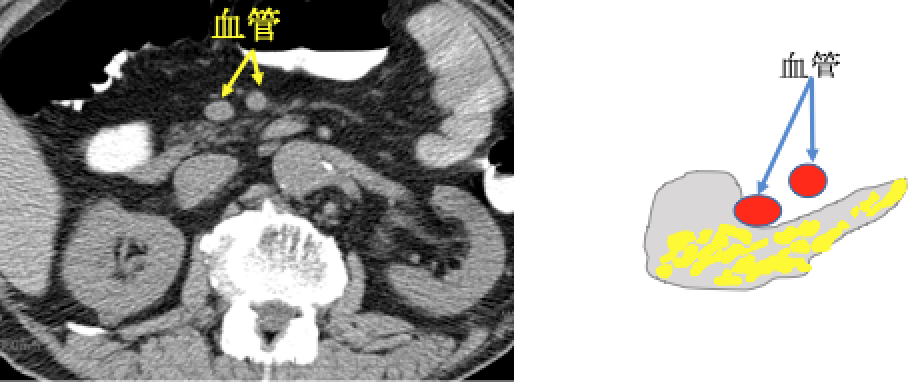

膵臓がんはすい管(消化液〈=すい液〉の通り道)から発生する膵管がんと言われています。 膵臓がんを発症すると、すい管が狭くなり、膵液が停滞します。その際に、主膵管拡張・膵のう胞(分枝膵管拡張)・脂肪変性(膵臓の凹みや痩せ)・腫れといった変化を引き起こします(膵臓がんの間接所見)。これにともなって、膵臓の炎症を起こしたり(みぞおちの痛み)、膵臓のはたらきが低下します(糖尿病の発症や悪化、味覚の変化、下痢など)。顕微鏡レベルの膵臓がん(上皮内がん)でも上記の間接所見や症状を伴うものがあることがわかってきました。膵臓がんが発生してから転移するまで約7年かかると言われております。この間に膵臓の形や膵管の変化をとらえることで早期の膵癌が発見できる可能性があります。

#⑤ 超音波内視鏡(EUS)

口から内視鏡を挿入し、胃や十二指腸の中から膵臓を間近で観察します。1cm以下の小さな膵臓がんをみつけることができます。顕微鏡レベルの膵臓がん(上皮内がん)周囲の炎症(線維化)もとらえることができます。外来で行える検査ですが、検査用の内視鏡が胃の内視鏡とくらべて太いため、鎮静剤を使用します。このためEUS検査を受けた日は車の運転はできません。